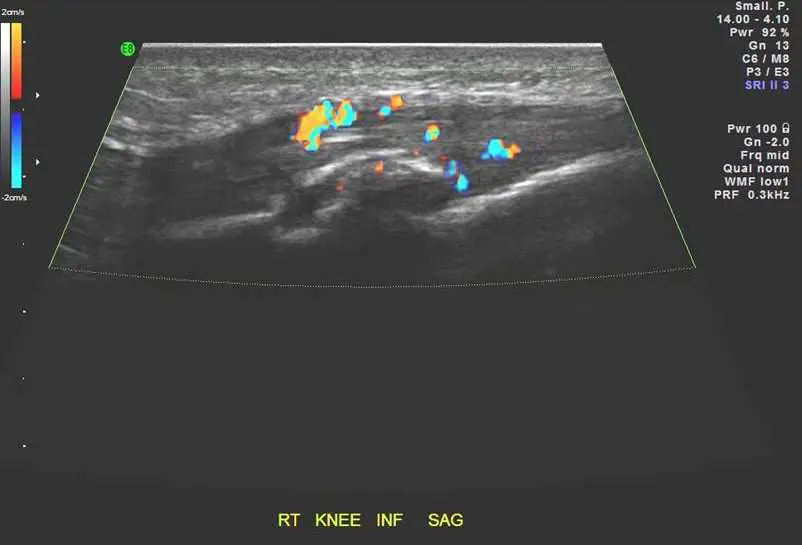

11 歲男童,主訴右膝疼痛,膝蓋前側之灰階及彩色杜卜勒超音波檢查如圖,最可能的診斷為何?

圖二(彩色杜卜勒超音波): 同一矢狀切面加上彩色杜卜勒訊號,在髕韌帶遠端插入脛骨粗隆處可見豐富的橙紅色及藍色血流訊號,代表此處有顯著的新生血管形成(neovascularization)/充血(hyperemia)。此為 OSD 活動性炎症的典型杜卜勒特徵,也是區別靜止期與活動期的重要指標。